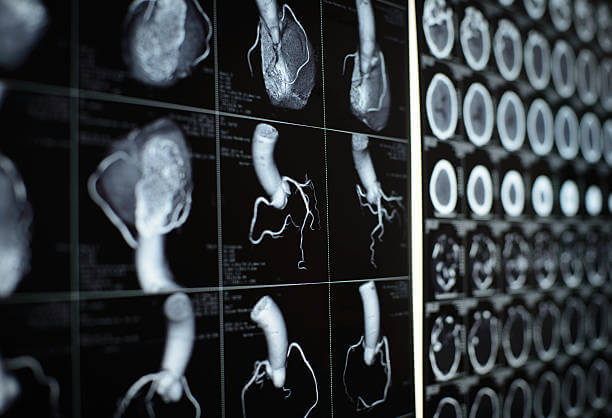

협심증 진단

- 환자의 증상과 의료 기록을 종합적으로 검토합니다. 가슴 통증, 호흡 곤란, 피로 등 협심증과 관련된 증상을 확인합니다.

- 의사는 환자의 혈압, 맥박, 호흡 등을 검사하여 신체적인 이상을 확인하고 심장 관련 소리나 이상 징후를 살펴봅니다.

- 혈액 검사를 통해 콜레스테롤 수치, 혈당 수치, 염증 표지자 등을 확인하여 협심증 가능성을 평가합니다.

- 심전도는 심장의 전기 활동을 측정하여 심장의 기능과 리듬을 평가합니다.

- 환자는 운동이나 약물을 통해 심장의 반응을 측정하는 스트레스 테스트를 받을 수 있습니다.